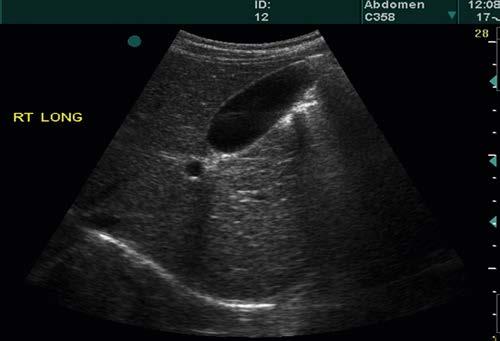

FIGURE 1-10 A, A modified form of a sector scan is produced when pulses and scan lines originate from different points across the curved top of a sector display. B, Abdominal scan with use of the scan format shown in A

different starting points (as in a linear image), but each pulse (and scan line) travels in a slightly different direction from that of the previous one (as in a sector image). In this example, the starting points form a curved line across the top of the scan, rather than a straight line, as in the linear scans shown in Figure 1-7.